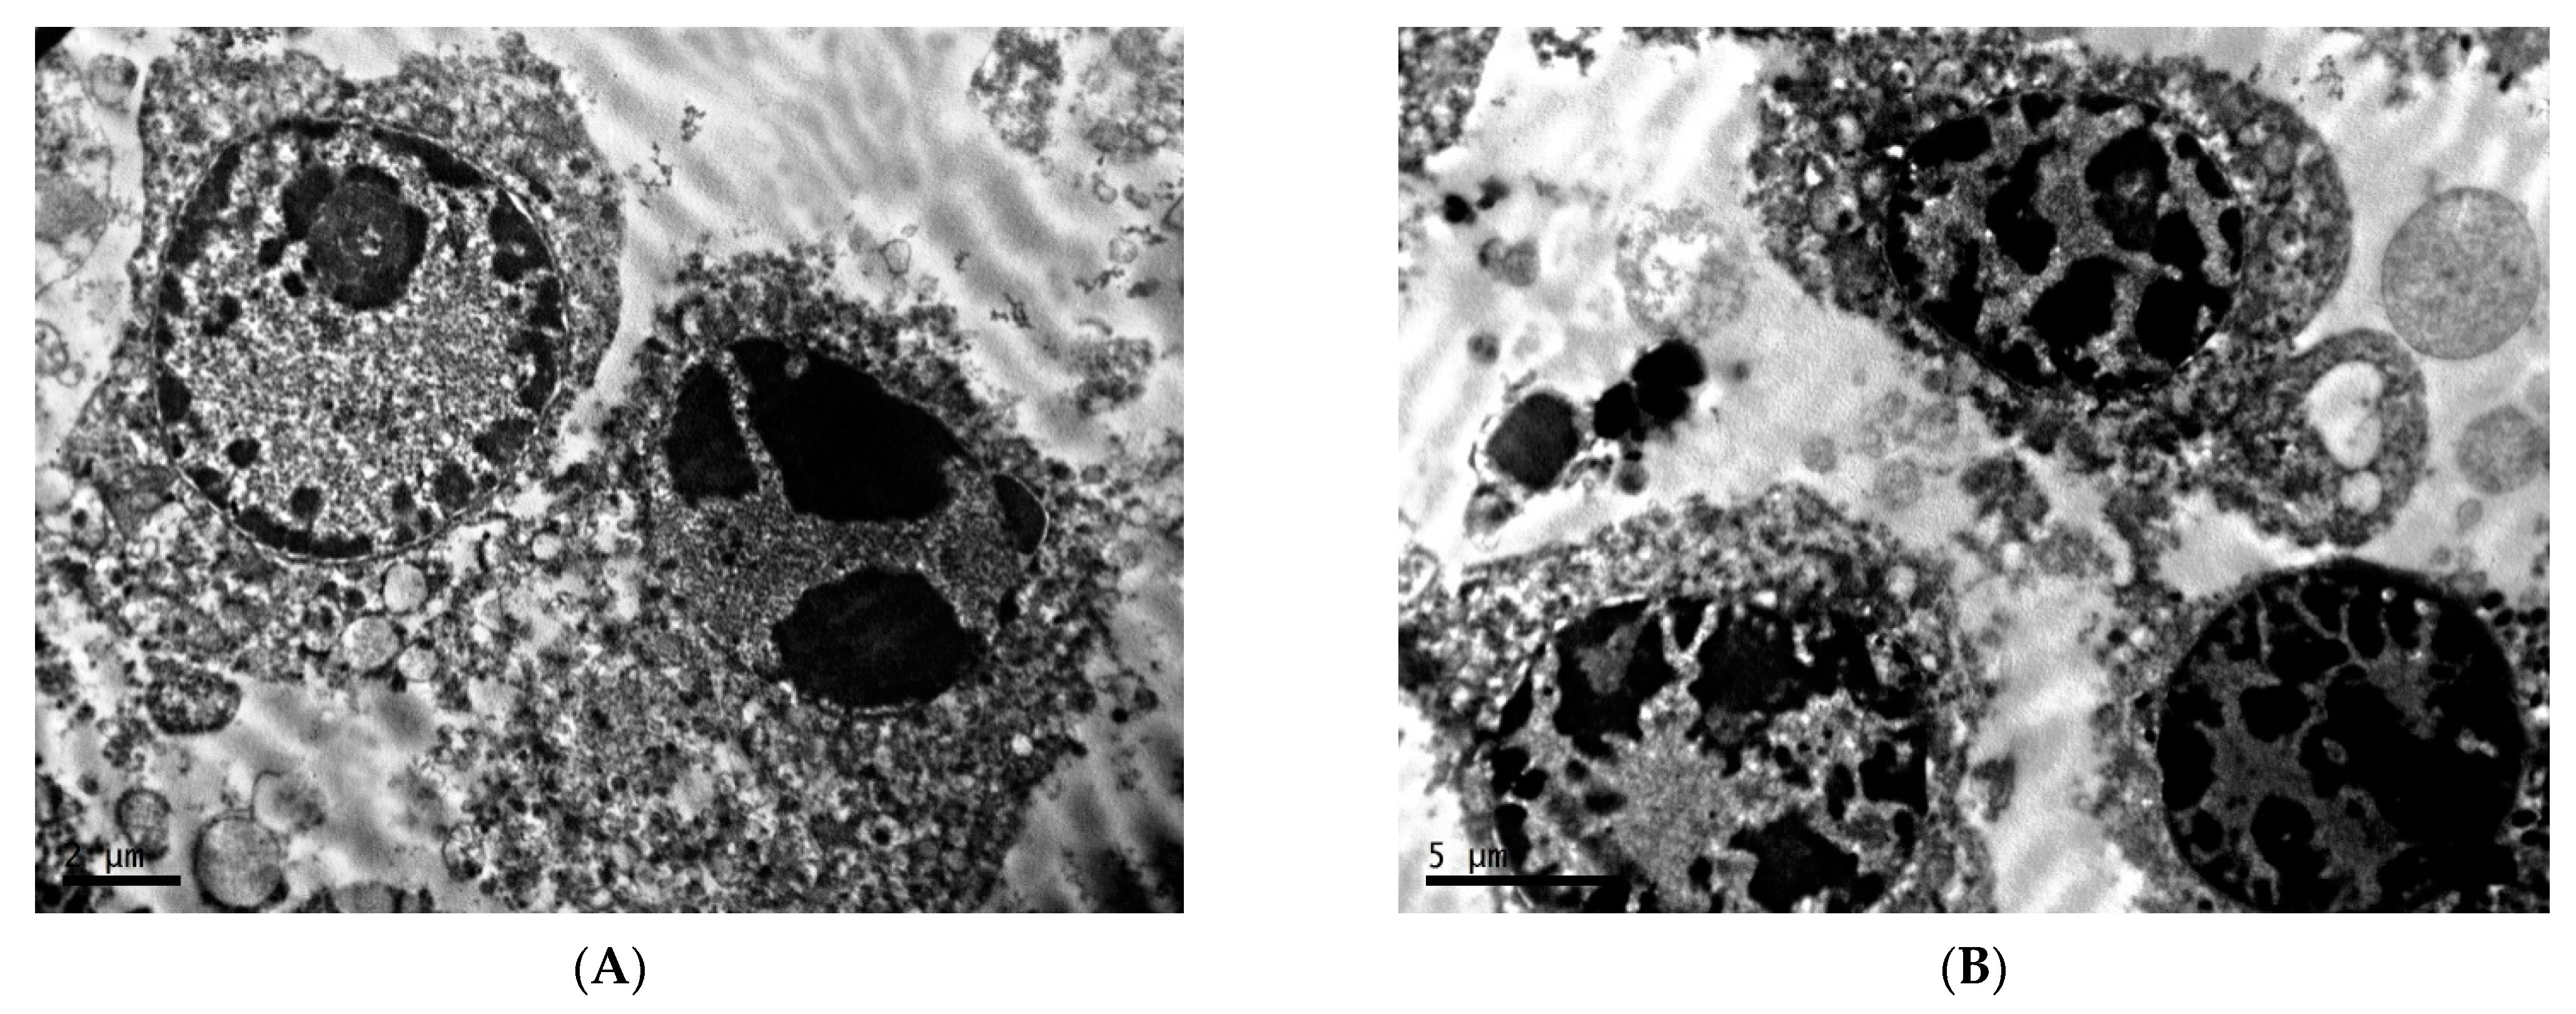

2.1. Ultrastructure of Transplantable Malignant Melanoma B16 in Conditions of Fixed Light Regime